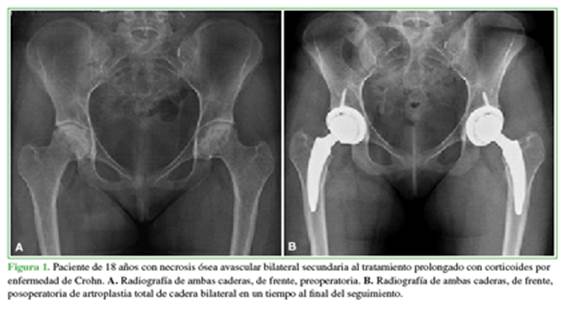

Después de obtener la aprobación de la junta ética de investigación de la institución, estudiamos retrospectivamente 26 ATC en 23 pacientes <20 años operados entre enero de 2006 y enero de 2021. Se incluyeron solo los casos de ATC con tallo femoral corto no cementados y un seguimiento mínimo de un año. Se excluyó a los pacientes con enfermedad oncológica activa relacionada con la patología, aquellos operados con tallos femorales cementados (8 pacientes) y tallos no cementados de tamaño estándar (2 pacientes). Luego de aplicar los criterios de selección, se excluyó a 10 pacientes; en consecuencia, se incorporaron 13 pacientes (16 caderas) sometidos a ATC primaria con un vástago corto no cementado tipo 2B con fijación cervico-metafisaria (MiniHipTM, Corin, Cirencester, Reino Unido) (Figura 1).11 Los datos demográficos de la serie se detallan en la Tabla 1.

Las causas que llevaron a la indicación de cirugía fueron: tres condrólisis idiopáticas, tres necrosis óseas avasculares (NOA) secundarias a epifisiólisis, dos secuelas de artritis séptica, una secuela de fractura de acetábulo, una displasia del desarrollo con secuela de osteotomía de pelvis fallida y seis casos (las tres bilaterales) de NOA inducidas por tratamiento prolongado de corticoides secundario a enfermedad de Crohn, lupus y leucemia linfoide aguda. En total, nueve (56%) de los casos corresponden a NOA secundaria a diferentes causas (Tabla 2, Figura 2). Ocho (50%) tenían cirugías previas a la ATC (Figura 3).